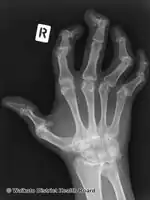

Right hand

Pain, swelling, or stiffness in one or more joints is commonly present in psoriatic arthritis.[3] Psoriatic arthritis is inflammatory, and affected joints are generally red or warm to the touch.[3] Asymmetrical oligoarthritis, defined as inflammation affecting two to four joints during the first six months of disease, is present in 70% of cases. However, in 15% of cases, the arthritis is symmetrical. The joints of the hand that is involved in psoriasis are the proximal interphalangeal (PIP), the distal interphalangeal (DIP), the metacarpophalangeal (MCP), and the wrist. Involvement of the distal interphalangeal joints (DIP) is a characteristic feature and is present in 15% of cases.

Along with the above-noted pain and inflammation, there is extreme exhaustion that does not go away with adequate rest. The exhaustion may last for days or weeks without abatement. Psoriatic arthritis may remain mild or may progress to more destructive joint disease. Periods of active disease, or flares, will typically alternate with periods of remission. In severe forms, psoriatic arthritis may progress to arthritis mutilans[5] which on X-ray gives a "pencil-in-cup" appearance.[1]